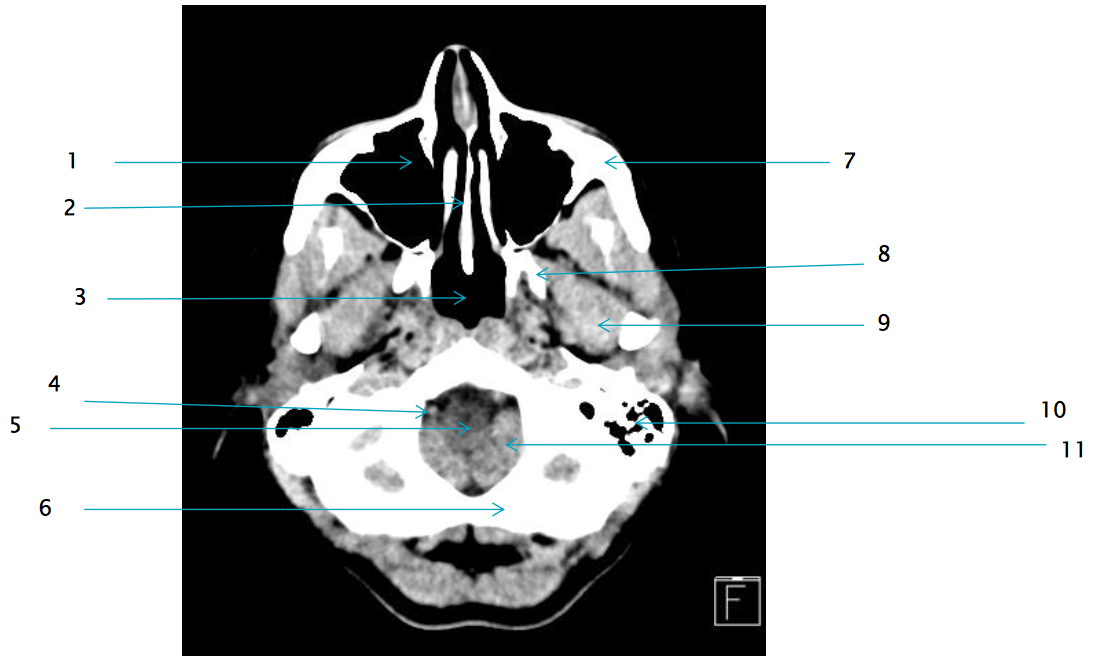

6

L occipital bone

7

L zygomatic arch

8

L lateral pterygoid plate

11

L Cerebellar tonsil

9

L lateral pterygoid muscle

1

R maxillary sinus

2

vomer

5

medulla oblongata

10

L mastoid air cells

4

R vertebral artery